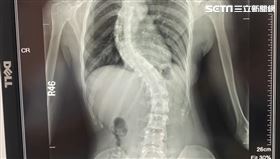

15歲妹身高僅145cm!X光一照「脊椎S側彎」

一名15歲少女生長遲緩合併脊椎側彎角度已達90度,心...

2024/05/10 12:46